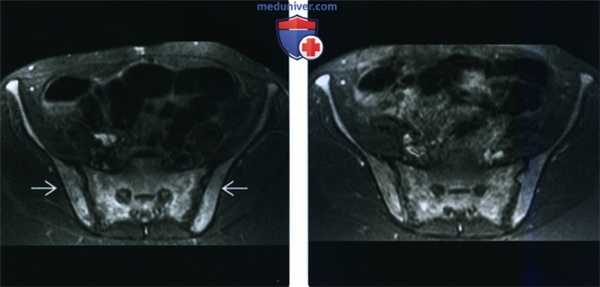

(Слева) МРТ, аксиальная проекция, режим STIR: у того же пациента в структуре костей таза и крестца определяется диффузный сигнал высокой интенсивности.

(Справа) МРТ, аксиальная проекция, режим Т1, с подавлением сигнала от жира, с контрастным усилением: на этом же срезе визуализируется диффузное накопление контрастного вещества теми же структурами. Изменения в зоне проксимальных отделов бедренных костей (включая эпифизы) и таза увеличивают вероятность инфильтративною поражения костною мозга. Результатами биопсии была подтверждена лейкемия. У этого пациента, предъявлявшего жалобы на диффузную боль в костях, патологических изменений при рентгенографии обнаружено не было, что является типичным вариантом развития событий. При помощи МРТ был установлен диагноз лейкемии.

(Справа) МРТ, аксиальная проекция, режим Т1 с подавлением сигнала от жира, с контрастным усилением: низкоинтенсивная «ползущая» зона некроза в структуре костного мозга, окруженная неоднородно накапливающей контрастное вещество костью и мягкотканными компонентами. Такой вид мягкотканного компонента с минимальным нарушением целостности кортикального слоя типичен для лимфомы. (Слева) MPT таза, аксиальная проекция, режим Т1 с контрастным усилением: у этого же пациента визуализируется контрастированный патологический очаг. На других изображениях визуализировался путь распространения патологического очага от нервных корешков L2 и L3 и по ходу бедренного нерва, что оказалось признаком эпиневрального метастазирования.